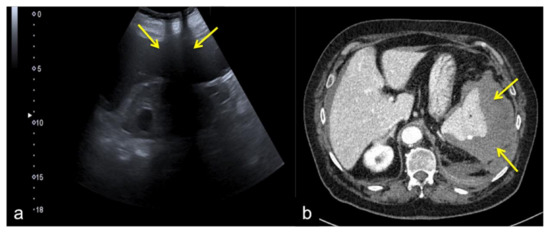

Figure 26. Coronal US scan of the left hypochondrium (a) shows partial exploration of the spleen with unrecognized traumatic injury (arrow) in a 22-year-old man investigated for trauma. On CT scan (b) it appears to be more evident (arrow).